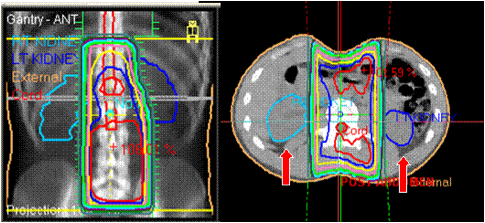

49+ Sbrt Radiation Vs Proton Therapy UK. It is possible to deliver high doses that destroy cancer cells, while minimizing damage to healthy tissue. With proton therapy, we're able to.

Proton therapy is a relatively new type of radiation therapy for treating cancer. Dose schedules have not yet been established. Traditional & holistic radiation therapy.

Proton therapy has been used in a limited number of patients with rectal, pancreatic, esophageal, and lung cancers. Learn about the advantages, disadvantages, and side effects. Nevertheless, 31 hospitals across the country have spent millions of dollars building proton therapy centers, and many advertise. Proton therapy aka proton beam therapy is an advanced type of radiation therapy that has revolutionized how tumors were targeted making the process more precise.